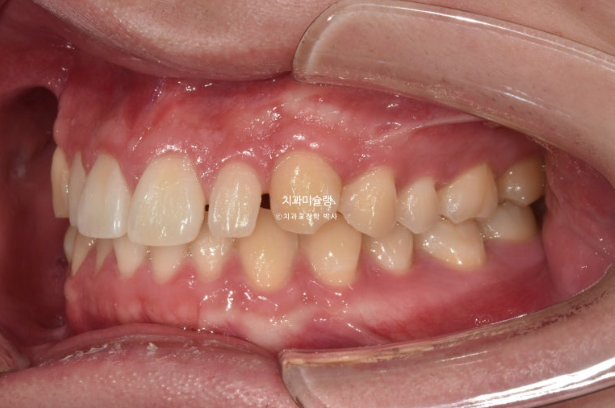

위 아래 중심선은 정확히 맞고

어금니 교합관계도 1급 입니다.

어금니 교합은 좋고 1급 교합관계를 보입니다.